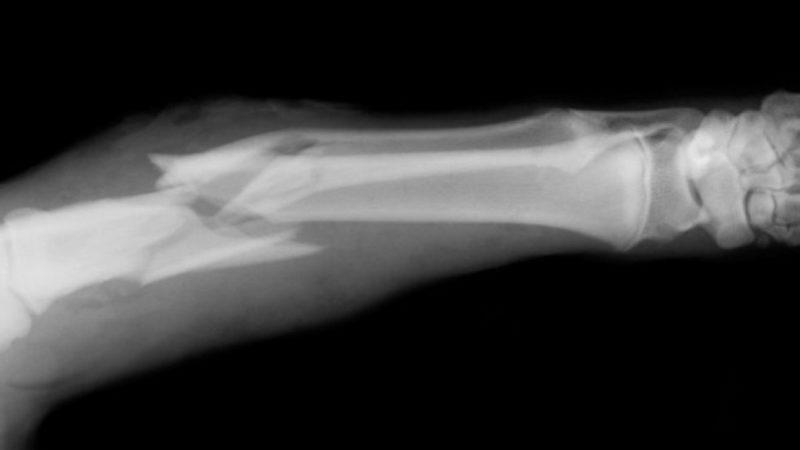

Fazlasıyla yanlış ve tehlikeli bir düşünce daha. Kırığın çapı, herhangi bir tendon yırtığı olup olmadığı bilinmeden kaderine terk etmek oldukça yanlıştır. Nitekim parmak kırıklarının iyileşme süreci 4-6 hafta periyodundadır ve bu süreçte kötü açılardan oluşan kırıklar geri dönülemez yaralanmalara sebep olabilir.